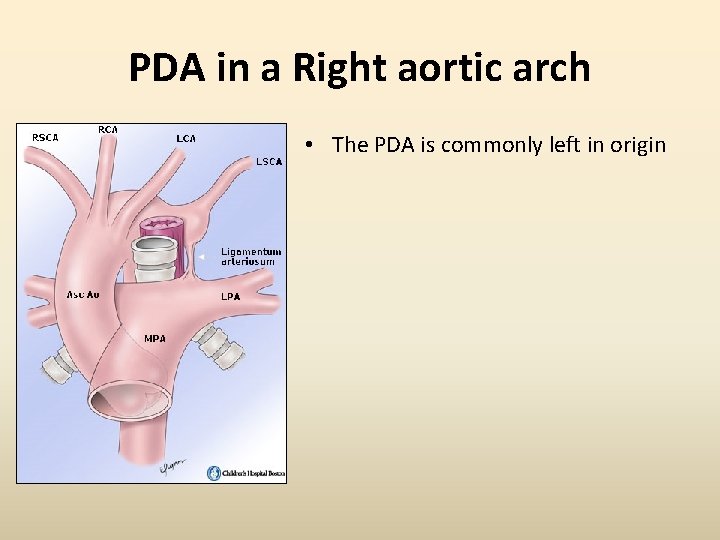

PDA in a Right aortic arch • The PDA is commonly left in origin